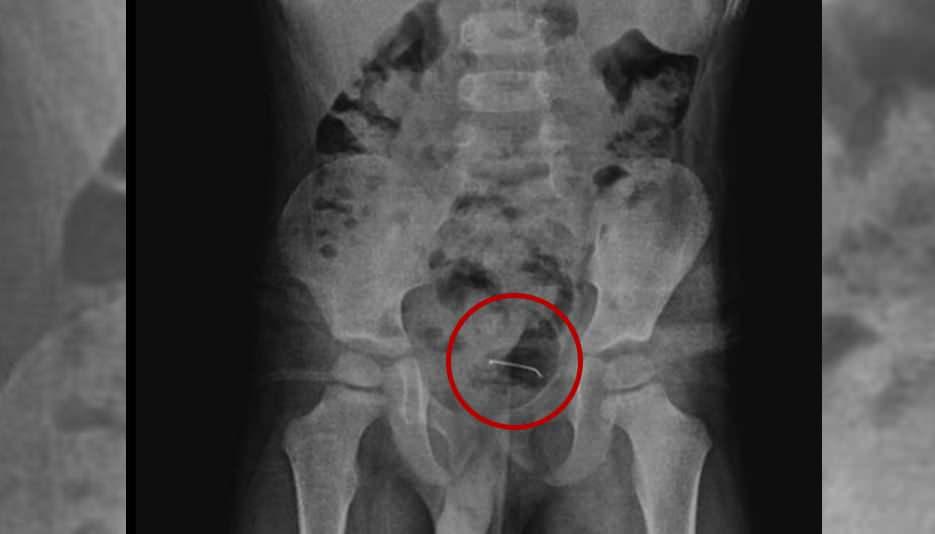

Bitlis’te, 5 yaşındaki bir çocuk oyun oynarken toplu iğne yuttu. 9 ay sonra şiddetli ağrılar yaşayan çocuk hastaneye götürüldü. Yapılan tetkikler sonucu yeri tespit edilen toplu iğne başarılı bir operasyonla alındı.

Bitlis’te oyun oynarken toplu iğne yutan 5 yaşındaki çocuk “yabancı unsur yutma” münasebeti ile ailesi tarafından hastaneye götürüldü. Hekimlerin incelemelerine karşın sonuç alamayan aile konuta geri döndü. 9 ay sonra şiddetli karın ağrısı yaşayan çocuk tekrar hastaneye götürüldü. Yapılan tetkikler sonucunda çocuğun mesane duvarında görülen ve toplu iğne olduğu tespit edilen yabancı husus başarılı bir cerrahi operasyonla alındı.

5 yaşındaki çocuğa yapılan tetkikler sonucunda, şiddetli karın ağrısına neden olan durumun mesane duvarına yapışan yabancı husus olduğu tespit edildi. Küçük çocuğun yuttuğu 3 santimetre uzunluğundaki toplu iğne başarılı bir operasyonla alındı.

3 SANTİMETRLİK TOPLU İĞNE BAŞARILI BİÇİMDE ÇIKARILDI

Kamçı, yabancı cismin bedenden olağan yollarla atılamadığını belirterek, “Bunun üzerine ameliyat kararı aldık. Ameliyatta cismin mesane duvarına yapıştığını gördük. Cerrahi operasyonla 3 santimetre civarındaki toplu iğneyi çıkardık. Hastayı birkaç gün takipte tuttuk. Genel sıhhat durumu düzgün olan hastamızı taburcu ettik.” ifadelerini kullandı.